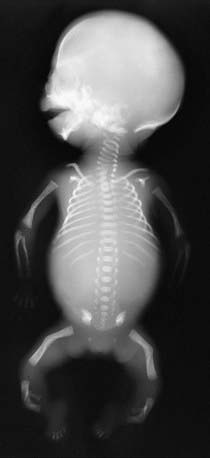

Apparent in newborn infants, campomelic dysplasia (OMIM 114290) is characterized by bowing of long bones (especially in the lower legs), short bones, respiratory distress, and other anomalies that include defects of the cervical spine, central nervous system, heart, and kidneys. Several cases of sex reversal of XY males have been reported. Radiographs confirm the bowing and often show hypoplasia of the scapulae and pelvic bones (Fig. 689-1). Affected infants usually die of respiratory distress in the neonatal period. Complications in children and adolescents who survive include short stature with progressive kyphoscoliosis, recurrent apnea and respiratory infections, and learning difficulties.

Figure 689-1 Radiograph in a fetus of 21 weeks’ gestation with campomelic dysplasia. Findings include a large skull with a small face; hypoplastic/absent scapular bodies; 11 ribs; poorly ossified thoracic pedicles; tall, narrow iliac wings; and short extremities with proportionately long, bowed femurs.

(From Slovis TL, editor: Caffey’s pediatric diagnostic imaging, ed 11, vol 2, Philadelphia, 2008, Mosby.)